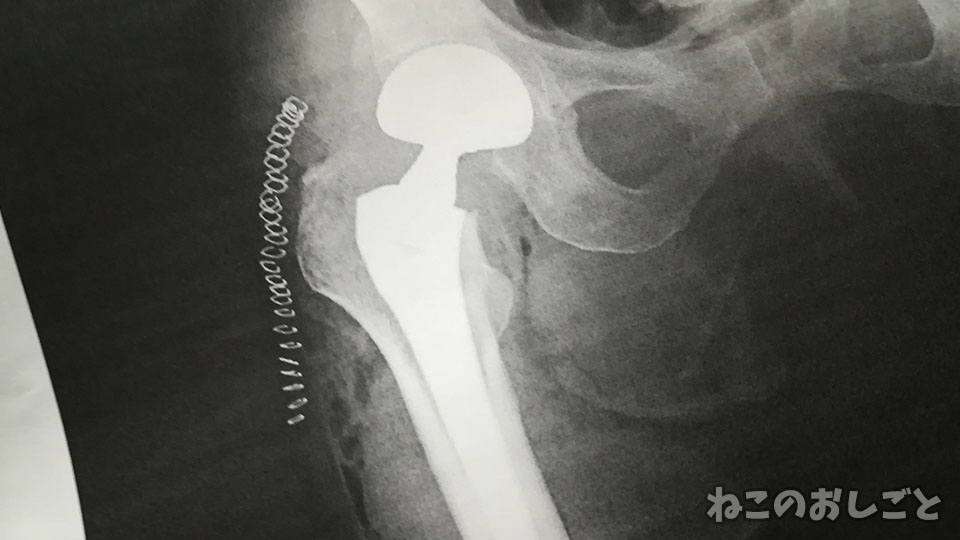

で、これ渡された!

きゃぁーっ!

ママロボ化されてるし!

猫月さん術後のレントゲン写真を

見ただけで2時間くらい意識を

失ってましたけど。